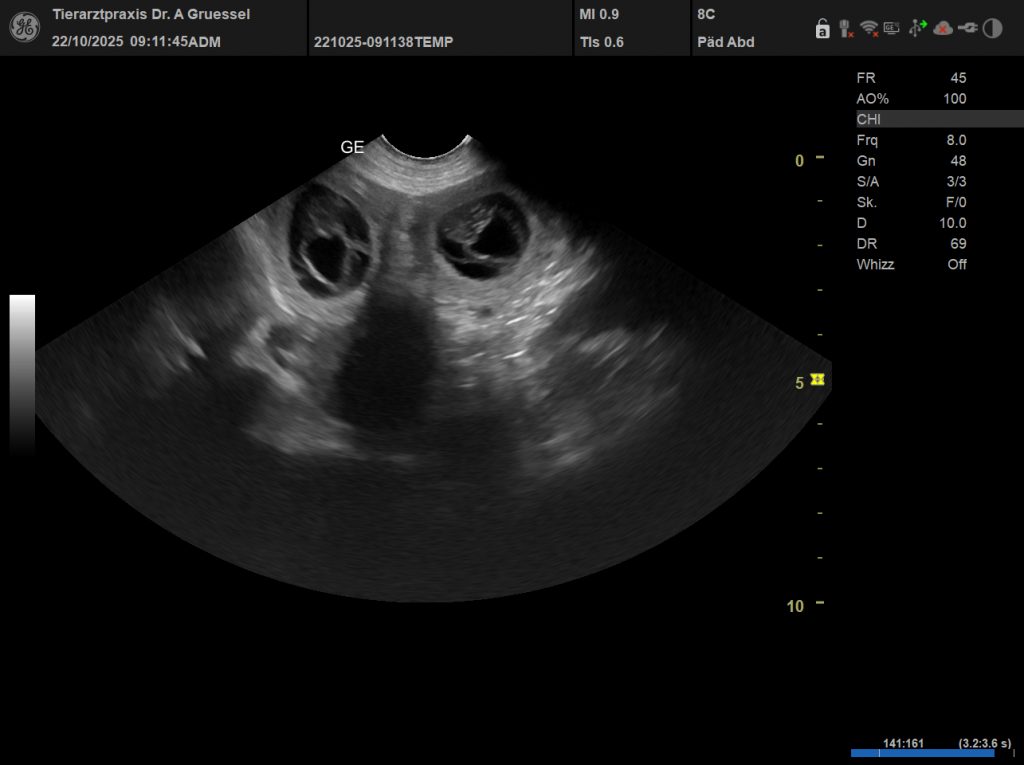

Der Ultraschall hat es bestätigt. Unsere Debby ist tragend und wir erwarten die Welpen in der letzten Novemberwoche. Vater ist Cyrano von der Maineiche.